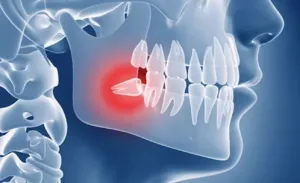

Здоров’я ротової порожнини значною мірою залежить від правильного розташування зубів і прикусу. Нерівні зуби...

У Dental Solutions https://www.dental-solutions.kh.ua/ ми розуміємо, наскільки важлива здорова та красива посмішка для кожного....